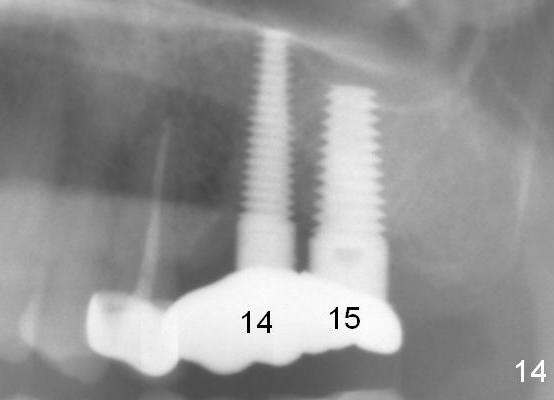

Bone density increases mesially (Fig.13 arrowheads) and distally (*) 1 year 2 months post cementation, 1 year 7 months postop, probably due to the response to the cantilever effect.

Partially due to severe food impaction on the right, the crown at #15 fractured and dislodged 2 years 6 months post cementation. The unipost was found to be loose. When the new crown at #15 was delivered, the abutment at #14 was mobile. After rebonding the abutment, the crown was redone. Fig.14 is taken after cementation at #14. The looseness of the abutments is the result of off-centered implant placement and bruxism.